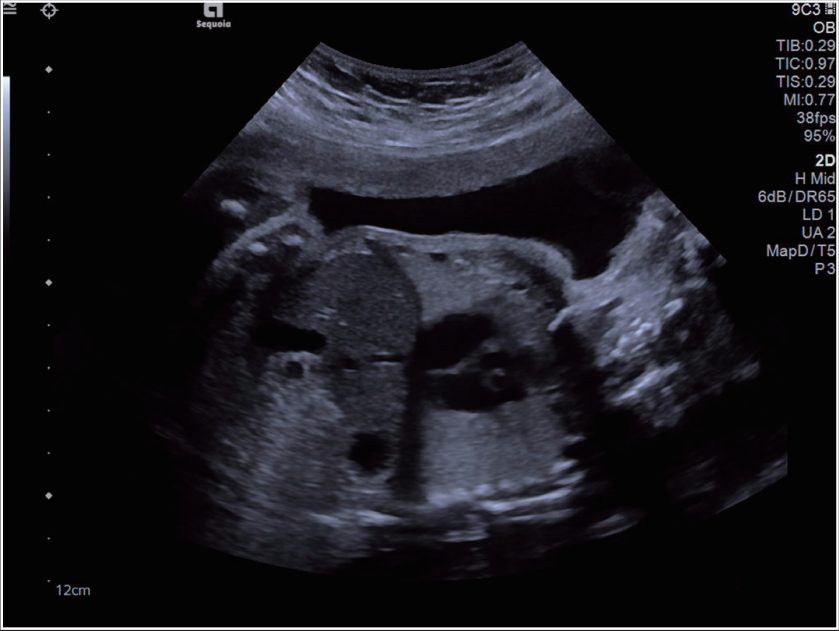

超声图像举例

dr在彩超什么意思一文搞懂X线、CT、MR、彩超检查的区别_https://www.jmylbn.com_新闻资讯_第3张

dr在彩超什么意思一文搞懂X线、CT、MR、彩超检查的区别_https://www.jmylbn.com_新闻资讯_第4张

超声的原理是用超声波穿透人体,当声波遇到人体组织时会产生反射波,通过计算反射波成像;

主要用于腹部、妇科、心脏等的检查;

多方向观察,实时成像;

超声受气体干扰大,对于肠道等含气体较多的器官,超声诊断准确率会降低,所以一般肠道检查使用肠镜;

彩超

孕妇检查的主要手段

彩超是孕妇诊断的主要方式;